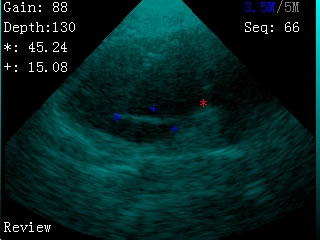

我司最新推出的V2型腕式B超,主机重量仅140克,看成目前全世界最轻的B超。

V2型腕式扇扫B超由主机、探头、外置电池、手握式键盘组成,重量只有140g(不含探头和电池)堪称全世界最轻的B超。

·图像清晰,测孕、测膘准确、快捷

·具有伪彩显示功能

-扫描方式:机械扇扫

-探头频率:3.5MHz/5MHz双频率可变频探头

-扫描深度:≥180mm,70、110、130、150、192mm五档可调